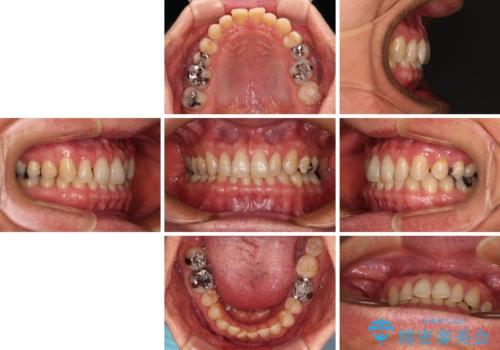

【モニター】ディープバイトで隙間の空いた歯列 ワイヤー装置での非抜歯矯正

- 前歯のデコボコと隙間の空いた歯列を気にして来院された患者様です。

下顎前歯が隠れるほどのディープバイトにより、強い咬合力と突き上げで上顎歯列に隙間が空いている状態でした。

手前に傾斜している奥歯をワイヤー装置で立ち上がらせ、咬み合わせの高さを挙上することで突き上げを解消し、空隙歯列を改善していくこととしました。

ディープバイトが改善され、睡眠時の食いしばりも緩和され、顎への負担が軽減されました。